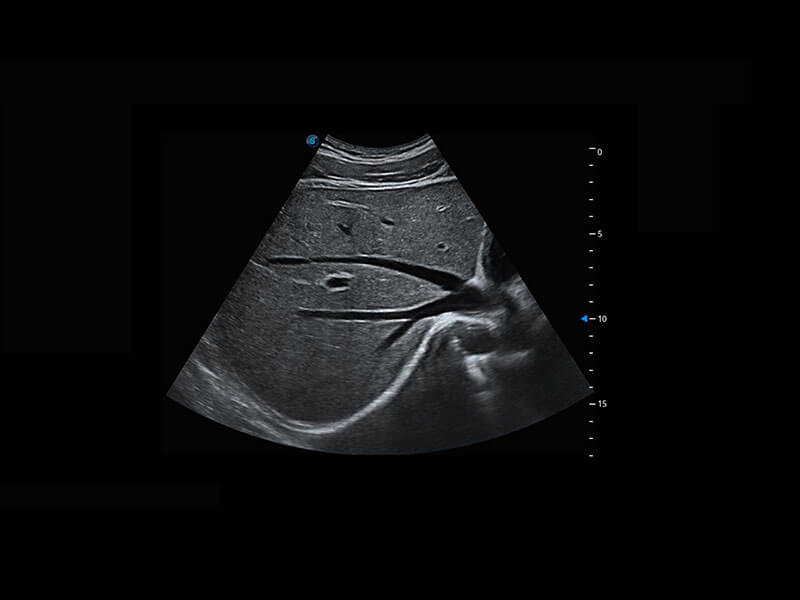

P60在胎兒早孕期超聲篩查中為您帶來(lái)優(yōu)異的圖像質(zhì)量。

早孕-胎心

高分辨率容積成像-早孕胎兒

胎兒體循環(huán)

光影成像-孕囊